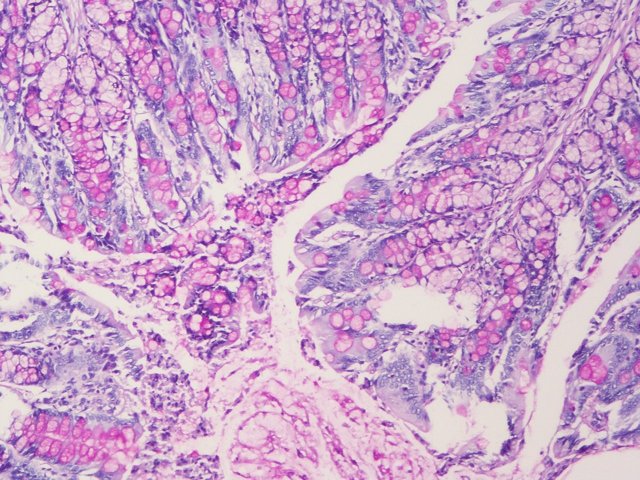

PAS染色又称过碘.酸雪夫染色,糖原染色;一般用来显示糖原和其他多糖物质。还可以观察肾小球基底膜、结肠杯状细胞中性黏液物质、阿米巴滋养体和霉菌的着色。

PAS阳性为红色;细胞核蓝色。

样片参考: